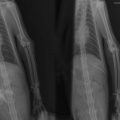

Диагноз:

- вывих локтевого сустава

- перелом локтевой кости

- межмыщелковый перелом плеча(?)